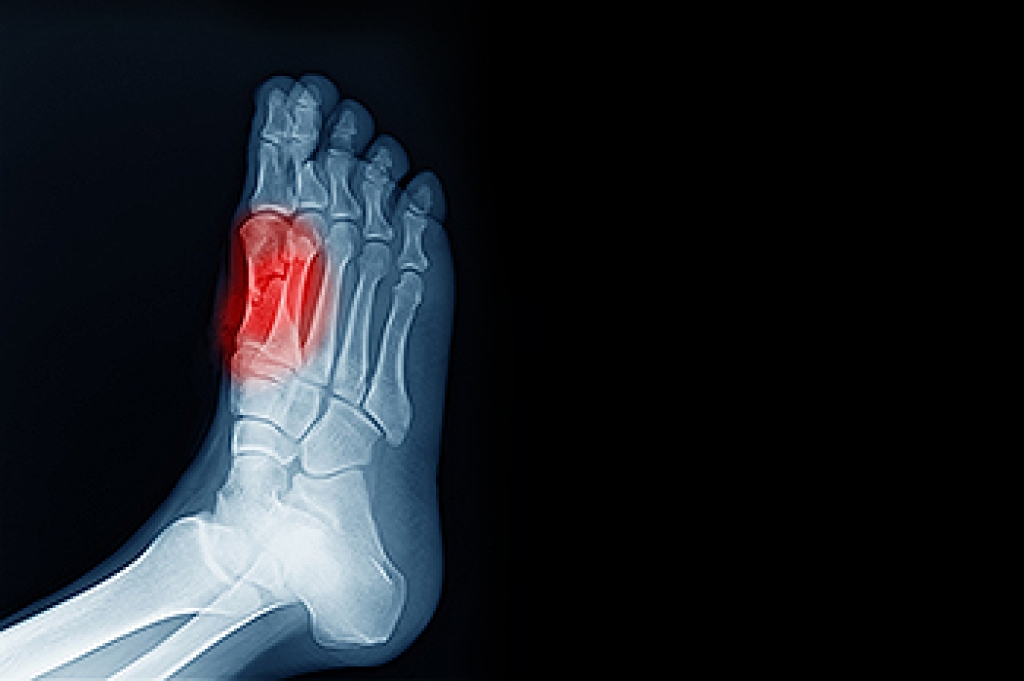

Tarsal tunnel syndrome, which can also be called tibial nerve dysfunction, is an uncommon condition of misfiring peripheral nerves in the foot. The tibial nerve is the peripheral nerve in the leg responsible for sensation and movement of the foot and calf muscles. In tarsal tunnel syndrome, the tibial nerve is damaged, causing problems with movement and feeling in the foot of the affected leg.

A physical exam of the leg can help identify the presence of tarsal tunnel syndrome. Medical tests, such as a nerve biopsy, are also used to diagnose the condition. Patients may receive physical therapy and prescriptive medication. In extreme cases, some may require surgery.